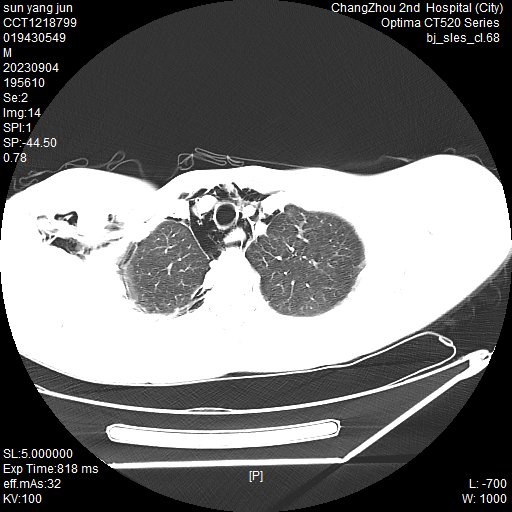

据悉,就诊过程中,这两个小伙子手捂胸口,神情痛苦,都有不同程度的疼痛感,通过胸部 CT 检查,医生告知这是出现了纵隔气肿。

常州二院胸心外科主任吴奇勇科普:「纵隔是左右纵隔胸膜之间的器官结构和结缔组织,而纵隔气肿则是在没有外伤、病菌感染、邻近脏器损伤的情况下,空气异常进入纵隔胸膜内结缔组织间隙之间,导致患者出现胸痛、干咳、呼吸困难、颈部吞咽困难等症状。纵隔气肿不仅会出现疼痛,还会出现皮下气肿。最常见的部位为颈部皮肤肿胀,也可发生面部、肩部等,触摸肿胀部位时,感觉像是握雪球的感觉,医学上称为『握雪感』。对于纵隔气肿这个疾病,胸部 CT 无疑是最快、最有效的辅助检查。值得特别注意的是,自发性纵隔气肿导致纵隔内压力上升,对心脏和大血管产生压迫,容易引发心衰,也可能引发严重的纵隔感染,这些都有可能危及生命。」